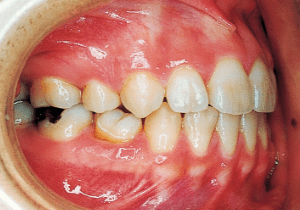

3 Year and month unknown Original

4 9-2-’85 At initial visit, molar relationship was a strong Class II.